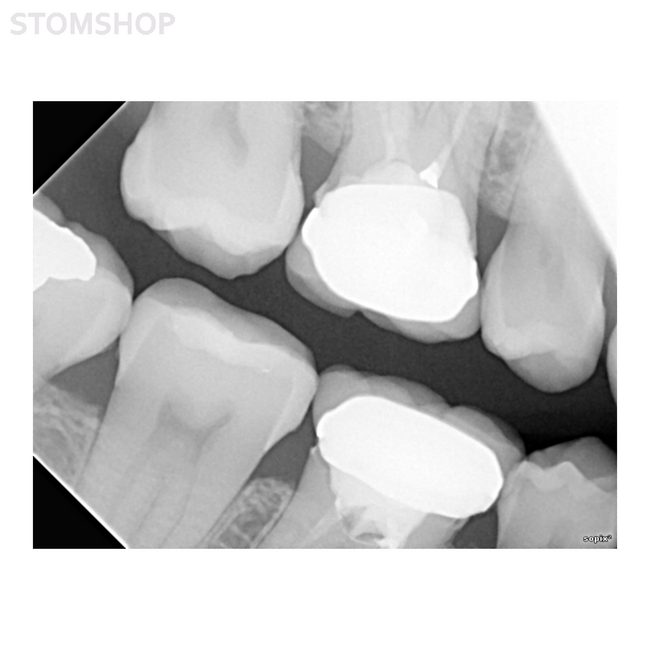

Прибор SOPIX2 представляет собой цифровую систему визиографии, используемую стоматологами. Сенсор (расположенный во рту пациента наряду с серебряной пленкой) получает рентгенограммы, создаваемые генератором. Затем он передает данные в подключенный к нему контрольный модуль, который, в свою очередь, передает информацию на экран компьютера.

Все снимки, сделанные системой SOPIX2, выводятся на экран при помощи программы SOPROImaging, поставляемой в комплекте. Данное ПО отображает, обрабатывает и хранит снимки, сделанные при помощи SOPIX2. Эксклюзивная технология ACE(Автоматический Контроль Экспозиции), разработанная SOPRO, наделяет систему огромной функциональностью. При помощи нее, SOPIX2 анализирует радиацию при каждой съемке, исключая риск передержки экспозиции.

Уникальным свойством визиографа SOPIX2 является запатентованный автоматический контроль выдержки - ACE, который предотвращает «переэкспозицию», что позволяет получать снимки стабильно высокого качества. Эта технология в реальном времени контролирует количество рентгеновского излучения, получаемого датчиком, и останавливает прием информации при достижении наилучшего качества изображения на снимке.

В датчике применяется плоский коллиматор из оптических волокон – технология FIBERPIXEL 2. Свет проходит через плоский массив оптоволоконных проводников, что позволяет исключить наличие шумов на полученном изображении. Реальное разрешение датчика: 18 пар линий на миллиметр (теоретическое – 25 пар линий на миллиметр).

Программный алгоритм обрабатывает данные, минимизирует артефакты и дефекты изображения, вызываемые наличием металлических объектов и применяемых в стоматологии материалов.